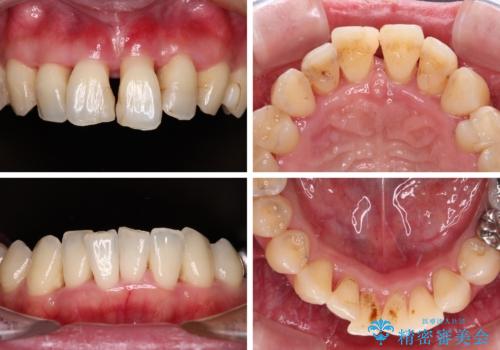

自他共に認める、非常に色白の患者様であったため、黄ばんだ歯の色を白くすることを希望されており、歯周病治療の該当部位に限らず、全顎的にオールセラミッククラウンにて補綴治療を行うこととしました。

多くの外科処置を行ったため、治療期間も長くなり、患者様の負担は非常に大きなものとなりましたが、明るく健康的な口元となり、患者様には大変満足していただけました。